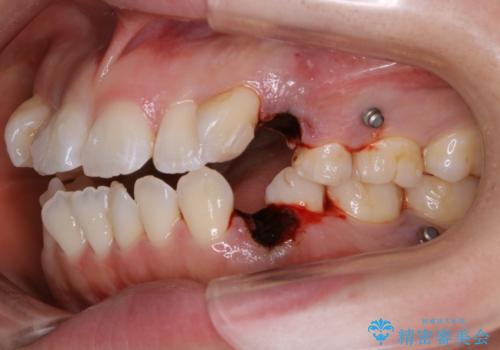

- 前歯のガタつき・噛み合わせの不調を主訴にご来院されました。

患者様のお仕事柄、目立たない装置で矯正したいとのご要望があり、今回はインビザラインを用いて抜歯矯正を行うこととなりました。

本来、抜歯によって得られる大きなスペースのコントロールはワイヤー装置の方が得意とされていますが、こちらの患者様のように犬歯が大きく手前に傾斜していて奥歯の噛み合わせにそれほど問題がないケースではマウスピース装置でも十分にコントロールできることが予測されます。

- 税込 ¥1,045,000- (インビザライン コンプリヘンシブパッケージ + マイクロインプラント費用)費用は治療当時の料金となります